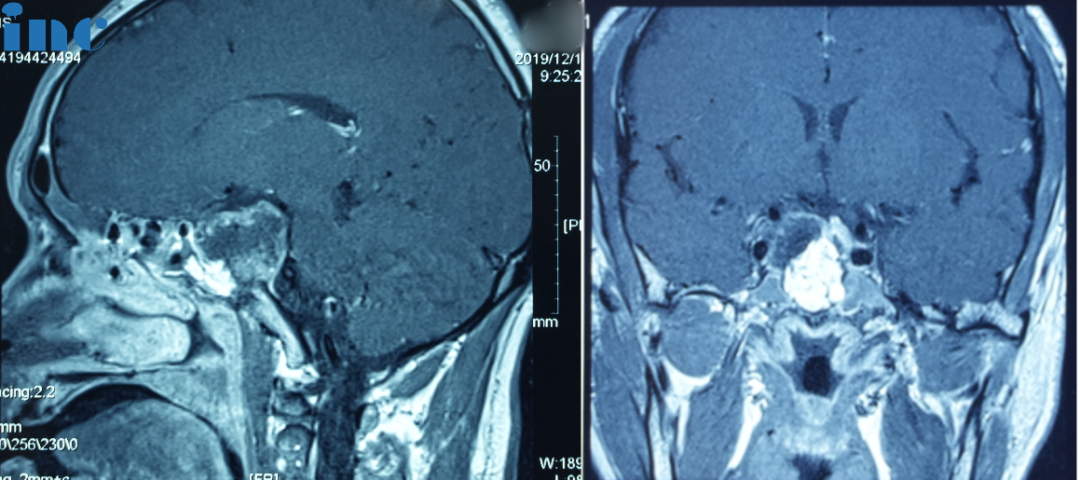

2019年:一開始經(jīng)鼻內(nèi)鏡手術(shù)

2019年10月患者無明顯誘因下突發(fā)視野缺損,伴視力下降,遂就診當(dāng)?shù)蒯t(yī)院。行頭顱增強(qiáng)MRI檢查,提示鞍區(qū)占位性病變,脊索瘤可能性大。

同年12月,行全麻下經(jīng)鼻神經(jīng)內(nèi)鏡下腫瘤切除術(shù),手術(shù)順利。術(shù)后病理提示“脊索瘤”。術(shù)后恢復(fù)尚可,視力、視野恢復(fù)良好。后因新冠疫情原因,未做術(shù)后復(fù)查。

2021年:二次開顱手術(shù)

2021年,患者再次出現(xiàn)視力下降伴視野缺損。于當(dāng)?shù)蒯t(yī)院行頭顱MRI檢查,提示“鞍區(qū)脊索瘤復(fù)發(fā)”。

二次開顱手術(shù)圖片

開顱手術(shù)圖片

2021年7月7日,全麻下行開顱鞍區(qū)腫瘤切除術(shù),術(shù)后病理為“脊索瘤(復(fù)發(fā))”。經(jīng)過較長(zhǎng)時(shí)間的術(shù)后恢復(fù),患者視力、視野恢復(fù)正常。